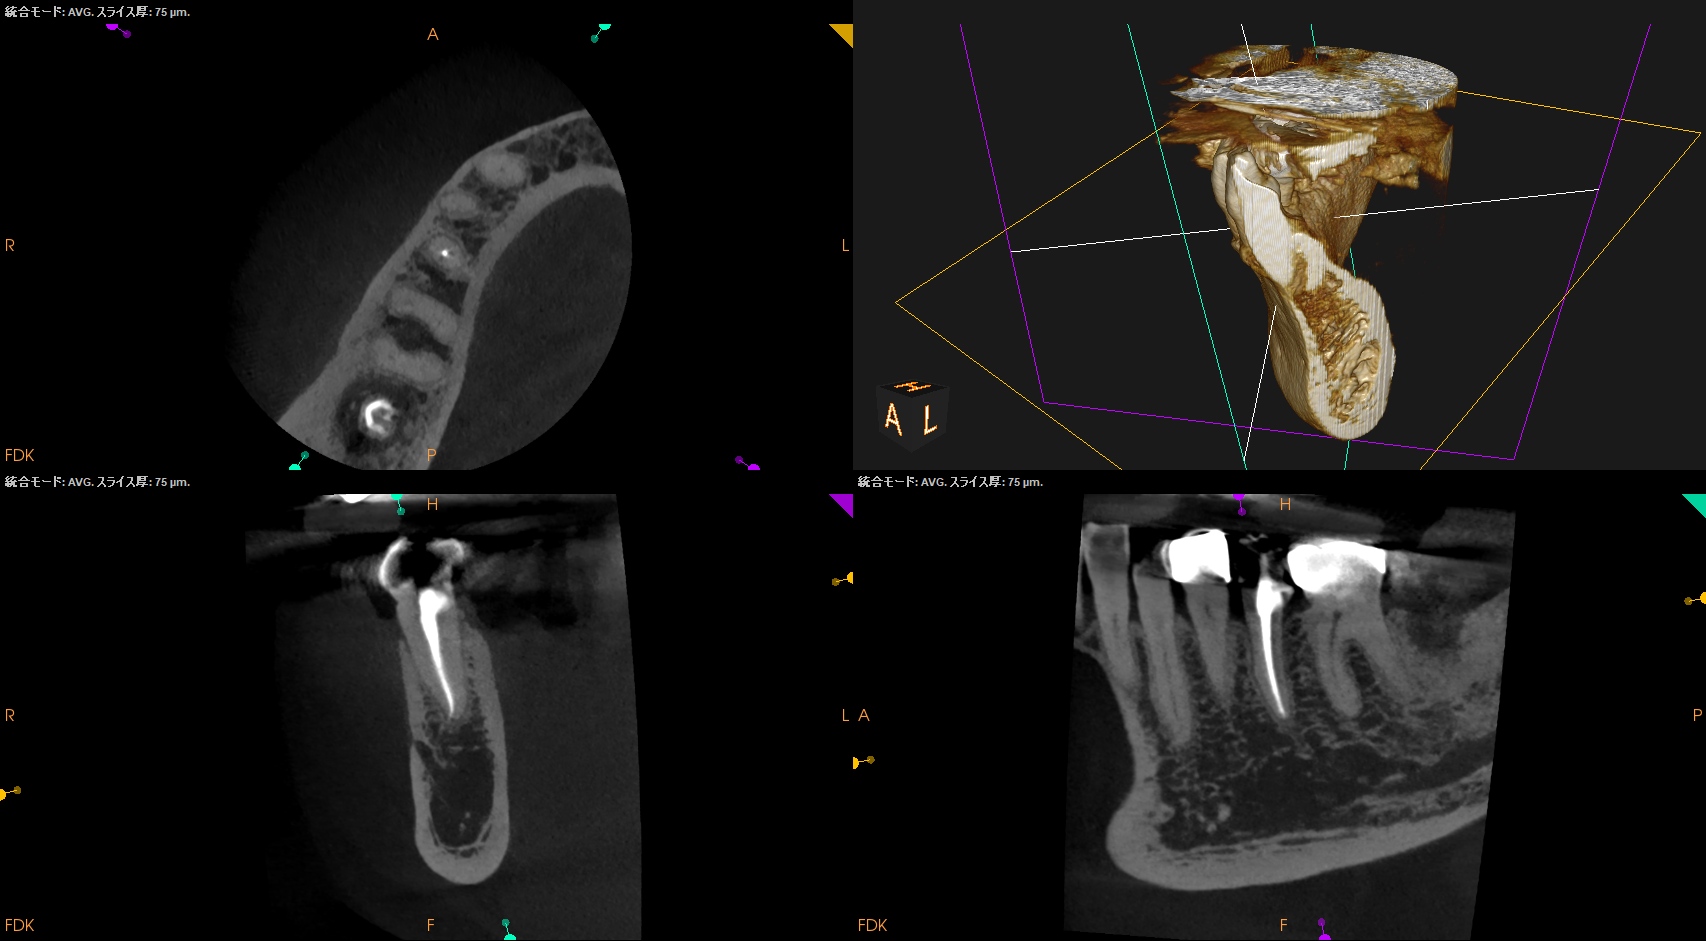

CBCT(2025.6.25)

が、根尖病変はない。

術後にPA, CBCTを撮影した。

パワープレイ的な治療だが、問題はないだろう。

問題があるとすれば…遠心の歯質が縁下カリエスであるということだ。

クラウンレングスニングが必要な旨をかかりつけ医には伝えた。